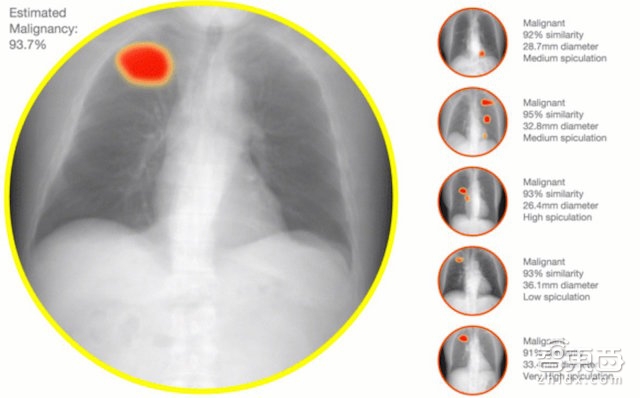

除了已經(jīng)比較成熟的醫(yī)療單據(jù)識別業(yè)務(wù)之外,醫(yī)拍智能目前還在拓展一條醫(yī)療影像領(lǐng)域的新業(yè)務(wù)線,通過深度學(xué)習(xí)、計(jì)算機(jī)視覺的技術(shù),為放射科醫(yī)生提供醫(yī)療影像(如X光、CT影片)輔助診斷,讓系統(tǒng)告訴醫(yī)生這張是肺癌病變圖像,那張是良性腫塊,降低醫(yī)學(xué)影像漏診率。

但由于醫(yī)拍智能是專門應(yīng)用在醫(yī)療領(lǐng)域的圖文識別,因此會(huì)比一般圖文識別技術(shù)存在一些挑戰(zhàn):比如醫(yī)學(xué)術(shù)語的識別與理解、病歷/化驗(yàn)單照片比一般圖片上的文字更為模糊,紙張也會(huì)更大等等。而醫(yī)拍智能最近在拓展的CT、X光等醫(yī)療影像診斷新業(yè)務(wù)線則對圖像處理、識別技術(shù)提出了更高的挑戰(zhàn)。